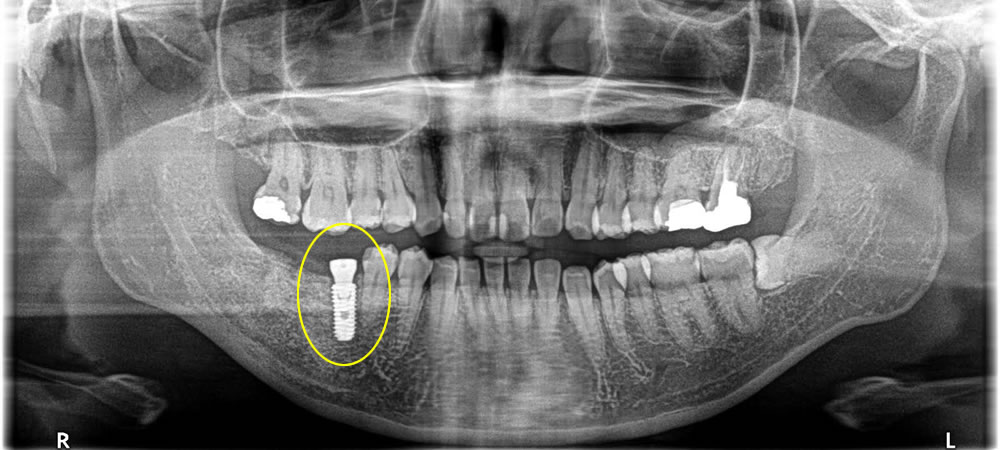

その後4ヵ月程おき、骨がしっかりと出来ていることを確認してインプラント治療を行いました。

上部構造の装着・治療完了

インプラント手術から3ヵ月後、しっかりと骨とオステオインテグレーション(結合)している事を確認し、上部の歯を作成しました。結果、しっかりと奥歯で噛む事ができるようになり、満足して頂く事ができました。